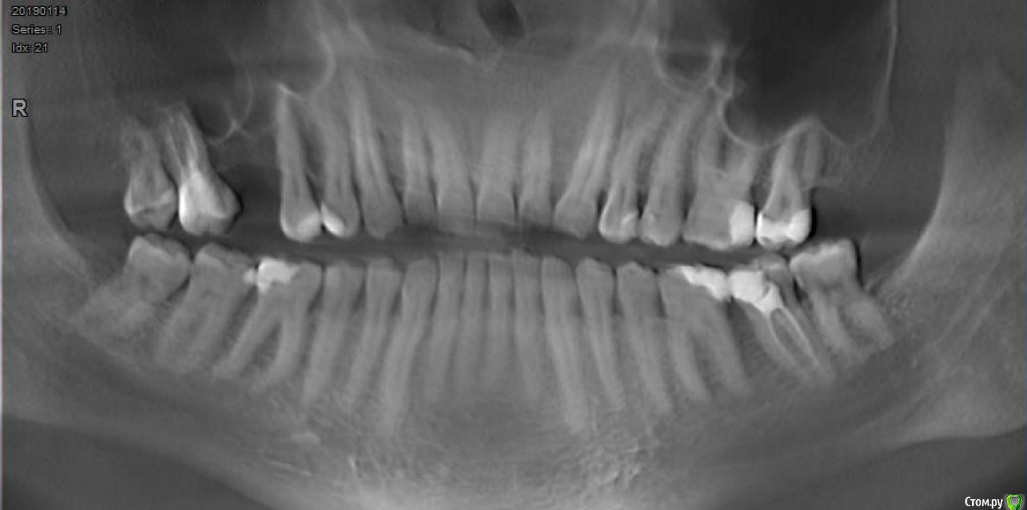

Мне 40 лет, прохожу в данный момент лечение брекетами в связи с открытым прикусом.

Изначально прикус был видимо глубокий, и на протяжении 15 лет беспокоили клиновидные дефекты на верхних резцах, которые постепенно прогрессировали.

Несколько лет назад изза сильного стресса появился бруксизм, резко увеличились клиновидные дефекты, и я некоторое время пользовался ночной капой, изза чего очень быстро появился открытый прикус.

Челюсти стали смыкаться углами зубов мудрости. Долго ходил по врачам, в основном предлагали сделать полное протезирование обеих челюстей, в итоге остановился на ортодонтическом лечении.

Удалили зубы мудрости, прикус стал заметно лучше, поставили брекеты на верх.

Первые 3 месяца все было отлично, пока не заметил, что верхняя семерка слева двигается вверх-вниз где-то на 0,5мм. То есть дуга тянет зуб из кости вниз, а при смыкании челюсти нижний зуб задавливает его обратно.

На следующем приеме врач наклеил на верхние моляры накладки, и выдал резинки для одевания на брекеты на передние верхние и нижние резцы. Первое время было нормально, нагрузка от жевания на двигающийся зуб благодаря накладкам исчезла, однако через некоторое время дуга вытянула этот зуб вниз, контакт при смыкании челюстей опять на нем и он опять двигается. Сейчас ситуация стала даже хуже, чем до удаления зубов мудрости, верхние резцы вообще не перекрывают нижние.

Да, еще мне показалось, что гипсовые модели деформированы сильнее, чем зубы в действительности. Контакт зубов при изготовлении слепков был на последних молярах, а модели почему-то смыкаются в середине челюсти на виде сбоку, а последний моляр висит в воздухе.